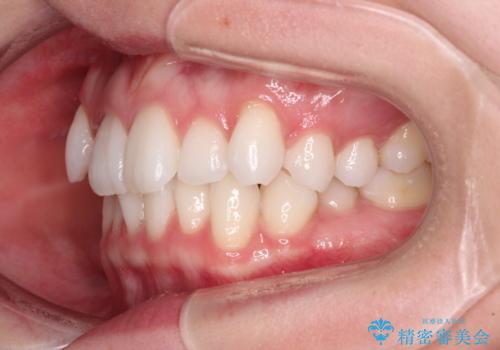

- 上下前歯のデコボコ、特に右上の八重歯を気にして来院された患者様です。

妊娠、出産の予定があり、毎月の通院が困難となる可能性があったため、インビザラインによる矯正治療を行うこととしました。

事前に親知らずを抜歯しておき、出産時期に困ることのないように準備をした上で治療を開始しました。

治療後半では悪阻によりマウスピースの装着時間が不十分となることもありましたが、それよりも前にしっかりと装着時間を守って治療を進めることができたため、特に気になるところなく治療を終えることができました。